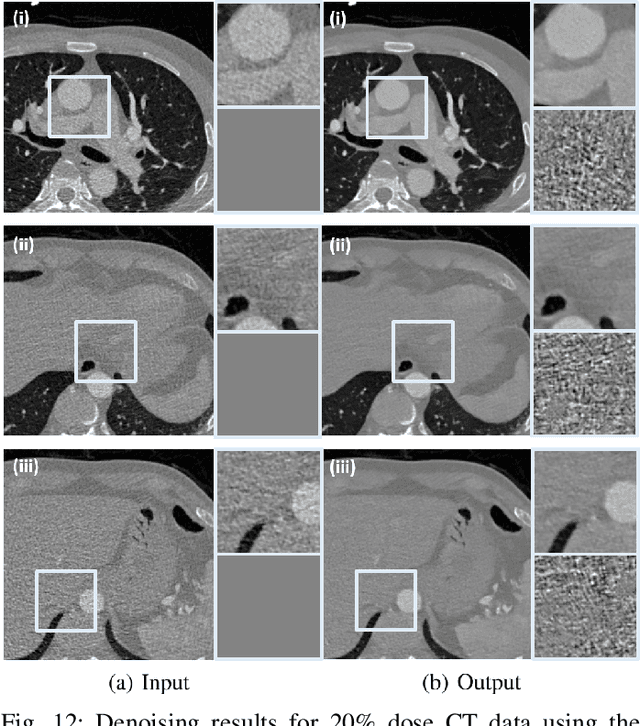

Recently, CycleGAN was shown to provide high-performance, ultra-fast denoising for low-dose X-ray computed tomography (CT) without the need for a paired training dataset. Although this was possible thanks to cycle consistency, CycleGAN requires two generators and two discriminators to enforce cycle consistency, demanding significant GPU resources and technical skills for training. A recent proposal of tunable CycleGAN with Adaptive Instance Normalization (AdaIN) alleviates the problem in part by using a single generator. However, two discriminators and an additional AdaIN code generator are still required for training. To solve this problem, here we present a novel cycle-free Cycle-GAN architecture, which consists of a single generator and a discriminator but still guarantees cycle consistency. The main innovation comes from the observation that the use of an invertible generator automatically fulfills the cycle consistency condition and eliminates the additional discriminator in the CycleGAN formulation. To make the invertible generator more effective, our network is implemented in the wavelet residual domain. Extensive experiments using various levels of low-dose CT images confirm that our method can significantly improve denoising performance using only 10% of learnable parameters and faster training time compared to the conventional CycleGAN.